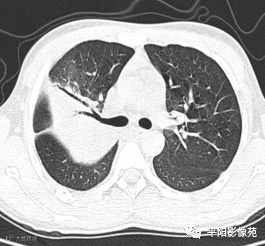

5天后复查X线片及CT:较前加重

10天后再次复查CT:较前有所好转